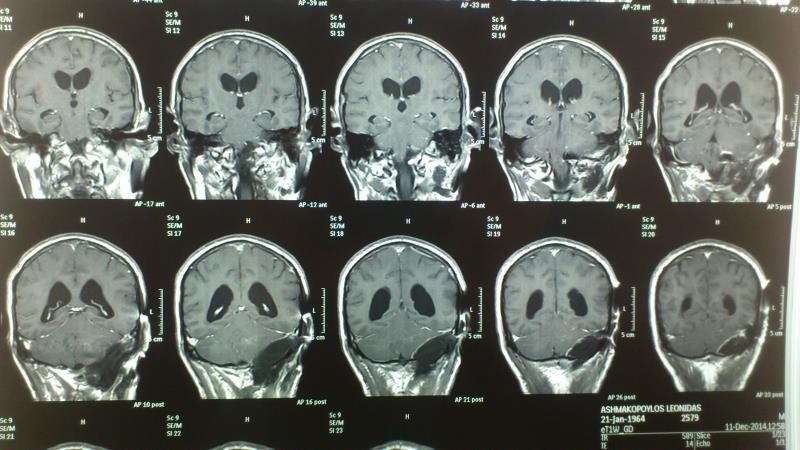

Ασθενής  άνδρας 55 ετών  προσήλθε λόγω αστάθειας βάδισης  και πάρεσης  των κατώτερων εγκεφαλικών συζυγιών  ( ΙΧ,Χ,ΧΙ ). Ο  έλεγχος με μαγνητική τομογραφία εγκεφάλου ανέδειξε εικόνα συμβατή  με μηνιγγίωμα ινιακού τρήματος με σημαντική πίεση επί του στελέχους. Ο ασθενής υποβλήθηκε σε αριστερή  Far Lateral Transcondylar προσπέλαση. Μετεγχειρητικά ο ασθενής παρουσίασε ήπια επιδείνωση της πάρεσης των κατώτερων εγκεφαλικών συζυγιών που ωστόσο αποκαταστάθηκε σταδιακά στα προεγχειρητικά επίπεδα Ο μετεγχειρητικός απεικονιστικός έλεγχος ανέδειξε ολική αφαίρεση του όγκου.

Μετεγχειρητικός απεικονιστικός έλεγχος